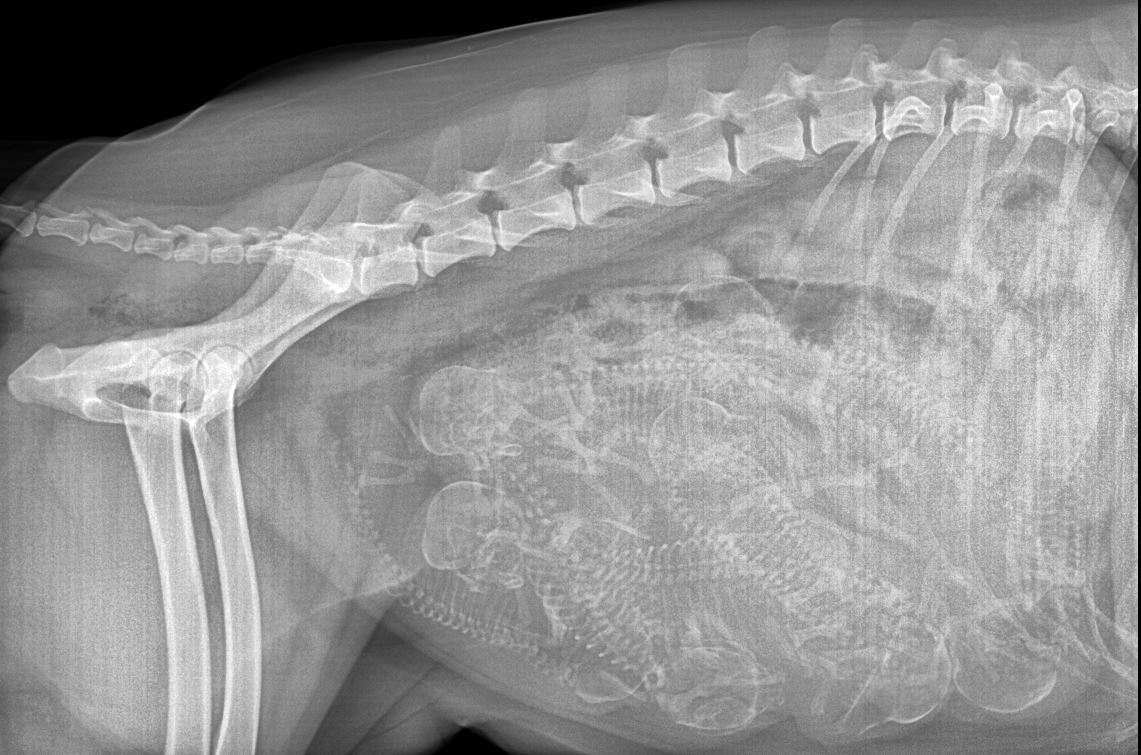

Wir sind schon gewachsen: (Röntgenbild)